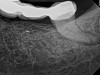

The second case study is that of a healthy 88-year-old woman who presented with significant bone loss on the mesial and apical aspect of tooth No. 18, which would suggest potentially a vertical fracture in the tooth (Figure 9 and Figure 10). The clinician had initially recommended extraction, which they informed the patient would likely be the best course of action, especially given that she had plenty of bone anterior to the tooth to place implants. When the recommendation of extraction was made to the referring dentist, he had some resistance because both he and the patient were interested in saving the tooth. Although the clinician initially stood firm on the recommendation, he received a call from the general dentist about a month later. He further expressed their desire to save the tooth, and he asked if the endodontist thought the new technology, the GentleWave Procedure, could be a solution. The informed consent was obtained and the patient was scheduled for treatment. Because the canal was quite calcified apically, a defined working length could not be determined. Obturation was performed using warm vertical condensation of gutta-percha.

Fig 9. Case 2: Significant bone loss on the mesial and apical aspect suggested a potential vertical fracture (Fig 9 and Fig 10). Radiographic images were taken immediately postoperatively (Fig 11) and 7 months postoperatively (Fig 12).

Fig 10. Case 2: Significant bone loss on the mesial and apical aspect suggested a potential vertical fracture (Fig 9 and Fig 10). Radiographic images were taken immediately postoperatively (Fig 11) and 7 months postoperatively (Fig 12).